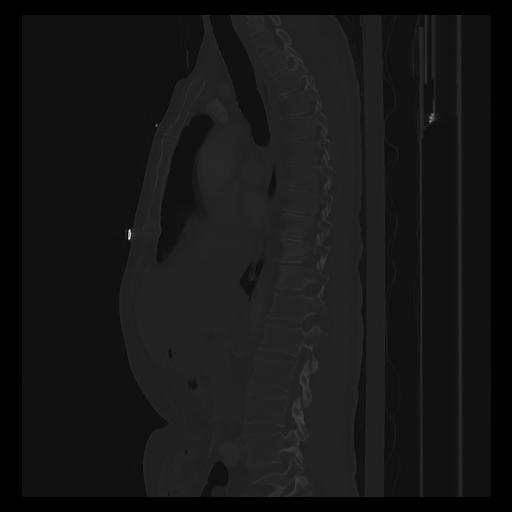

33 PULMON,CE,Sagittal,3.000,PULMON,Sagittal,